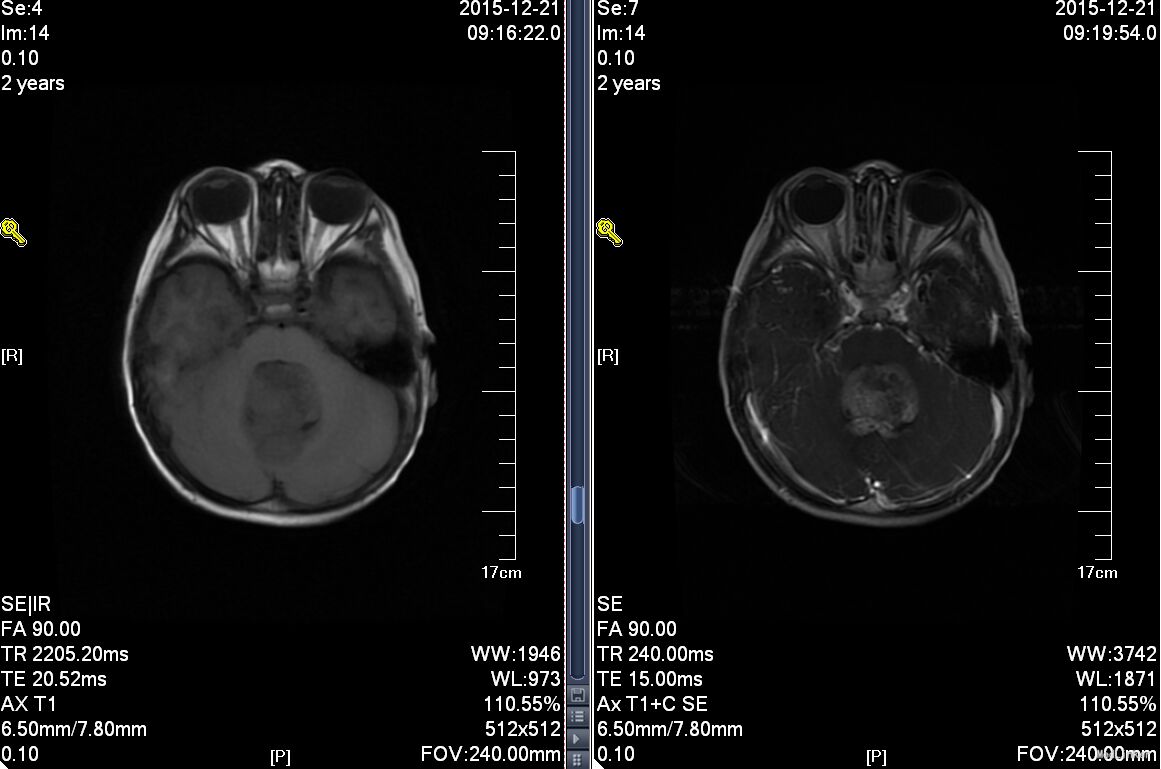

患儿女,1月9天,因“皮肤黄染1个月,发现精神差、拒食1天”入院。患儿于1月前开始出现皮肤黄染,未作处理,至今未退,1天前发现精神状况差,伴拒食,不哭,间有吐奶,非喷射性,无发热,无抽搐,无咳嗽、流涕,无喘憋及呼吸困难,无昏迷,无腹胀、腹泻,今至我院门诊就诊,为求进一步治疗拟“败血症?”收入院,患儿发病以来,大小便正常,无解白陶土样大便。为第3胎第3产,孕足月顺产出生,否认出生时窒息、抢救史,出生体重2.9kg,生后至今母乳喂养,母亲进食蔬菜少。入院体查:T:36.6℃,P:110/分,R:30次/分,WT:3.5kg,发育正常,营养中等,嗜睡状,精神差,反应差,全身皮肤中度黄染,无皮疹,前囟紧张,稍胀,双侧瞳孔不等大,右侧直径约2mm,左侧直径约4mm,对光反射迟钝,口唇无发绀,咽部无充血,颈软无抵抗,双肺呼吸音粗,未闻及干湿性啰音,心音有力,律齐,各瓣膜听诊区未闻及杂音。腹软不胀,肝脾肋下未触及,腹壁反应存在,肠鸣音正常,脊柱、四肢无畸形,右侧肌张力增高,左侧肌张力正常,生理反射存在,病理反应未引出,脑膜刺激征阴性。入院查:头颅CT结果回报提示1、左侧额颞顶部急性硬膜下血肿,脑肿胀,考虑合并脑疝形成可能,2、蛛网膜下腔出血。凝血四项:APTT36.1秒,Fbg:3.00g/L,INR1.13,PT15.1秒,TT17.4秒,血常规:17.2*10^9/L,红细胞2.83*10^12L,网织红细胞计数0.032,血红蛋白09g/L,血小板711*10^9/L;血生化:白蛋白49.1g/L,超敏C反应蛋白2.3mg/L,二氧化碳23.9mg/L,钙2.40mmol/L,谷丙转氨酶79U/L,谷草转氨酶60U/L,肌酐12umol/L,肌酸激酶同工酶75U/L,钾3.91mmol/L,镁0.92mmol/L,钠126mmol/L,尿素氮2.60mmol/L,葡萄糖8.03mmol/L,羟丁酸脱氢酶501U/L,球蛋白14.6g/L,乳酸脱氢酶551U/L,葡萄糖-6磷酸脱氢酶4919U/L,间接胆红素126.5umol/L,直接胆红素76.3umol/L,总胆红素202.8umol/L,磷酸肌酸激酶135U/L。该患儿最有可能的诊断是?诊断依据?如何确定下一步的诊疗方案?